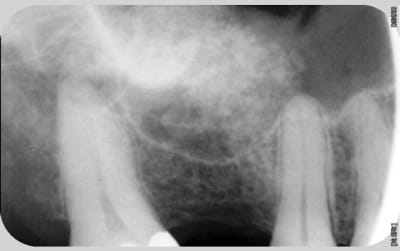

nouvelle radio cette semaine

Tekka n'assume toujours pas.

c'est des krestals? Ça n'a pas l'air dramatique sur la radio. Une petite caractérisation qui me parait logique vu la connexion.

On n'a pas les mêmes critères d'exigences. Perdre 4 mm d'os sur 12 soit 1/3.

Attends, sur ces radios t'as 4 mm de perte osseuse? Les vis de cicatrisation sont en place non? Je devine la jonction implant/vis et y a quasiment pas de perte sur tes dernières radio. Enfin je connais pas bien le krestal et la forme de la vis.

Je veux dire, elle est où la perte osseuse sur cette radio? Mais tu as raison, on ne doit pas avoir les même exigences.

La cratérisation est visible beaucoup plus haute: surtout au sondage. L'os que tu vois est en palatin, en vestibulaire, il n'y a plus rien sur cette même longueur.

Sur la molaire, tu ne vois rien aussi.